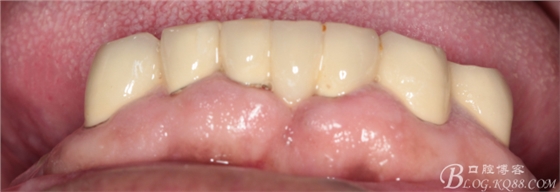

修復(fù)兩年后患者復(fù)診

44作為覆蓋基牙保留完好,牙周狀態(tài)良好,附著體基牙有一定的牙齦萎縮,

上頜套筒冠基牙無(wú)松動(dòng),對(duì)比做牙前得到較大改善

下頜附著體 義齒有菌斑殘留

上頜義齒有煙斑殘留